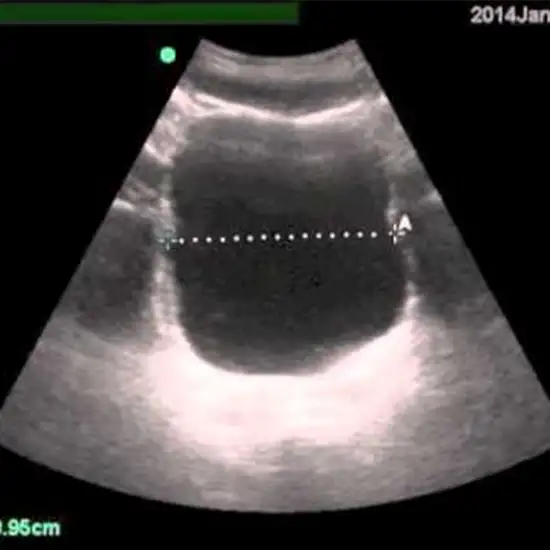

- How accurate are bladder scan devices